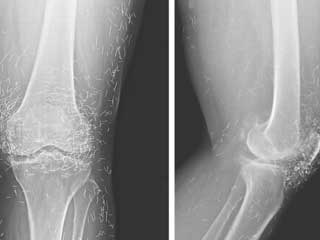

عثر الأطباء بعد إجراء صورة بالأشعة السينية، لركبة امرأة كورية 65 عاماً، على معدن من الذهب، ومئات من إبر الوخز الصغيرة، التي بقيت في أنسجتها، وذلك عندما كانت تعاني من آلام شديدة في المفاصل.

ونقلت صحيفة "فوكس نيوز"، أن المرأة كانت قد شخصت إصابتها بمرض هشاشة العظام، وهو مرض تتدهور معه الغضاريف والعظام الموجودة في المفاصل، ما يؤدي إلى الآلام والتصلب.